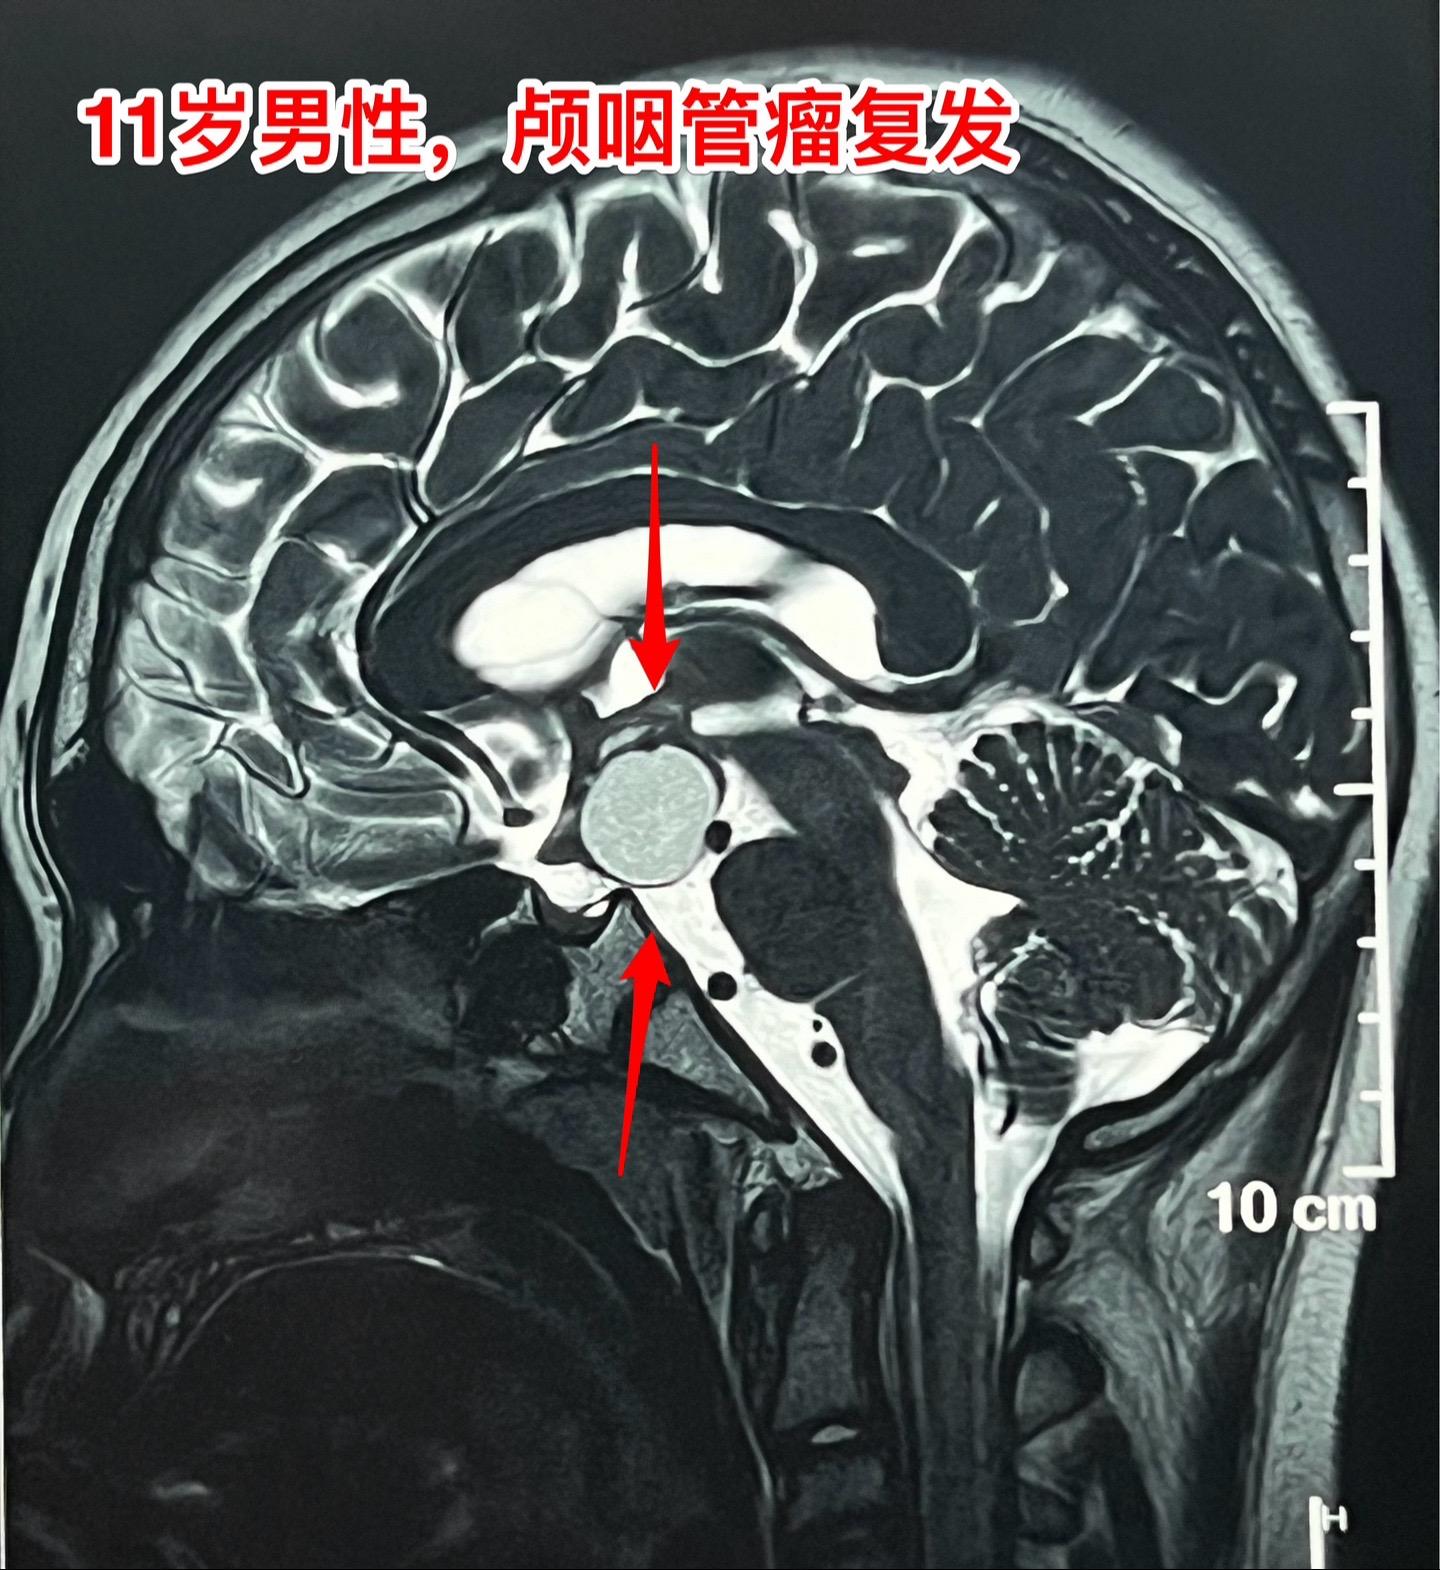

国庆节长假后第一天完成两个手术。一个手是33岁女性,来自云南省香格里拉。因左眼视力下降,到医院检查发现鞍区肿瘤,怀疑是颅咽管瘤。病人没有内分泌功能障碍。影像学上肿瘤是实性的,没有钙化,而且可以看见垂体信号。到底是什么肿瘤呢?今天手术中取肿瘤标本作快速冰冻病理检查,报告是垂体瘤。肿瘤得到完全切除,手术后病人视力好转了。 另一个手术是11岁男孩子,颅咽管瘤复发。经原切口翼点入路将肿瘤完全切除。术前磁共振只看见一个圆形肿瘤,术中发现除了这个肿瘤外还有5个散在的钙化斑,均得到完全切除。这样的散在钙化斑是潜在的危险因